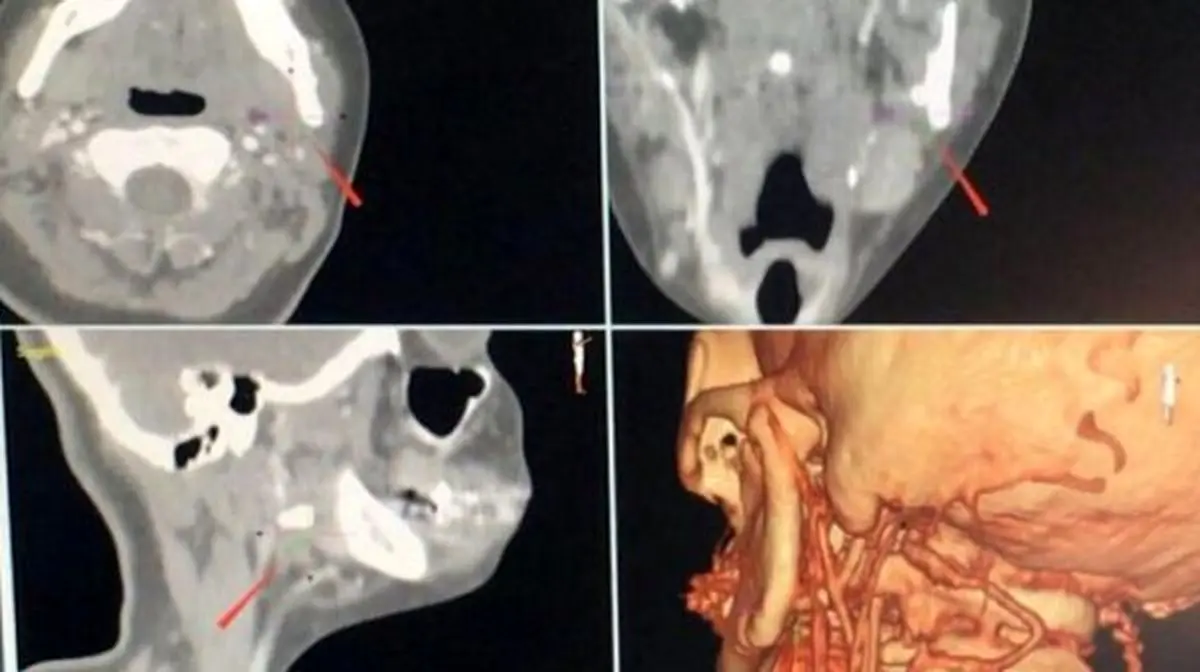

بيژن موحديان عطار با بیان اینکه اين عمل جراحي بر روي این بيماري درشهرديگري به صورت ناموفق و به روش معمول انجام شده بود گفت: در این عمل از دستگاه Navigation همراه با ورودي DICOM سيتي اسكن سه بعدي با كنتراست استفاده شد.

وی افزود: دراين عمل، موقعيت دقيق جسم خارجي و ارتباط آن با عروق ژوگولار(سیاهرگی که خون دی اکسید کربن دار را از مغز به قلب میرساند) و كاروتی (سرخرگی که از قلب خون را به مغز می رساند) با خطای كمتر از یک دهم ميليمتر شناسايی شد.

دانشيار و مديرگروه جراحی دهان، فك و صورت دانشگاه علوم پزشکی اصفهان افزود: سپس با انتخاب كوتاه ترين و ايمن ترين مسير خروج، برای جلوگيری ازآسيب به عروق حياتی دراطراف اين جسم، با استفاده از تنها يك برش ٥ميليمتری در زمان ٢٠دقيقه جسم خارج شد.